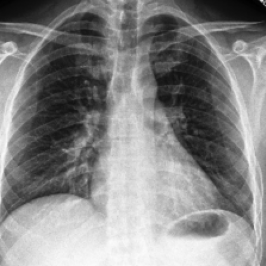

Waterbirds (Sagawa et al., 2020) is an image classification dataset where bird types are associated with a spurious background attribute (water or land). CelebA (Liu et al., 2015) is an image classification dataset, where hair color is an imbalanced attribute with respect to gender. MultiNLI (Williams et al., 2018) is a text benchmark of categorizing two sentences as entailing each other, contradicting each other, or neutral. The spurious correlation is between negation words like “never” and the “contradiction” label. CivilComments (Borkan et al., 2019) is a toxicity text classification dataset containing underrepresented demographic groups. CheXpert (Irvin et al., 2019) is a large-scale medical dataset of chest radiographs with rare pathologies, especially amongst certain minority groups.

We follow standard model choices and dataset splits consistent with prior work (Liu et al., 2021; Kirichenko et al., 2022; Qiu et al., 2023): for Waterbirds, CelebA, and CheXpert, we use ResNet-50 (He et al., 2016) pretrained on ImageNet1k (Russakovsky et al., 2015), for MultiNLI and CivilComments we use BERT (Devlin et al., 2018) pre-trained on Book Corpus and English Wikipedia data.

• J. Irvin, P. Rajpurkar, M. Ko, Y. Yu, S. Ciurea-Ilcus, C. Chute, H. Marklund, B. Haghgoo, R. Ball, K. Shpanskaya, J. Seekins, D. A. Mong, S. S. Halabi, J. K. Sandberg, R. Jones, D. B. Larson, C. P. Langlotz, B. N. Patel, M. P. Lungren, and A. Y. Ng (2019) CheXpert: a large chest radiograph dataset with uncertainty labels and expert comparison. External Links: 1901.07031, Link Cited by: §C.1, §5.1.